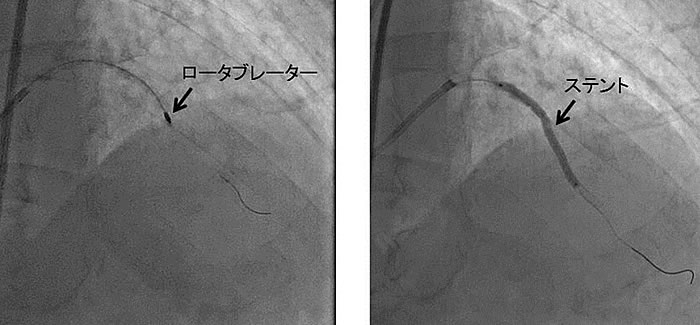

これはワイヤーの先端に弾丸型のダイアモンドチップ(burr)が取り付けられており、そのチップを一分間に15万回以上回転させて、固い粥腫を赤血球大にまで粉砕して流してしまう、という道具です。

では、まず実例です。

上左図の矢印部はまだ造影剤が注入されていないにもかかわらず、血管に沿って黒く見える部分があり、これが石灰化の存在を示しています。上右図において、その石灰化の部位に狭窄が存在しています。拡張不良が予想される所見です。

最終的に、良好な拡張が得られました。また、理論上は細かく粉砕された病変は血管に詰まることはないはずなのですが、必ずしもそううまくはいかず、胸痛が長く続いたり、ひどい場合は心筋梗塞になってしまうこともあります。ですから、心筋梗塞を繰り返したために残された心臓の機能の少ない人や、著しく病変が長いために削られる病変の量が多いと予想される病変には、ロータブレーターによる治療はあまり適していません。ロータブレーターは基本的にプラーク表面付近の硬い組織を削り取る道具であり、その後、バルーンカテーテルおよびステント留置が行われます。